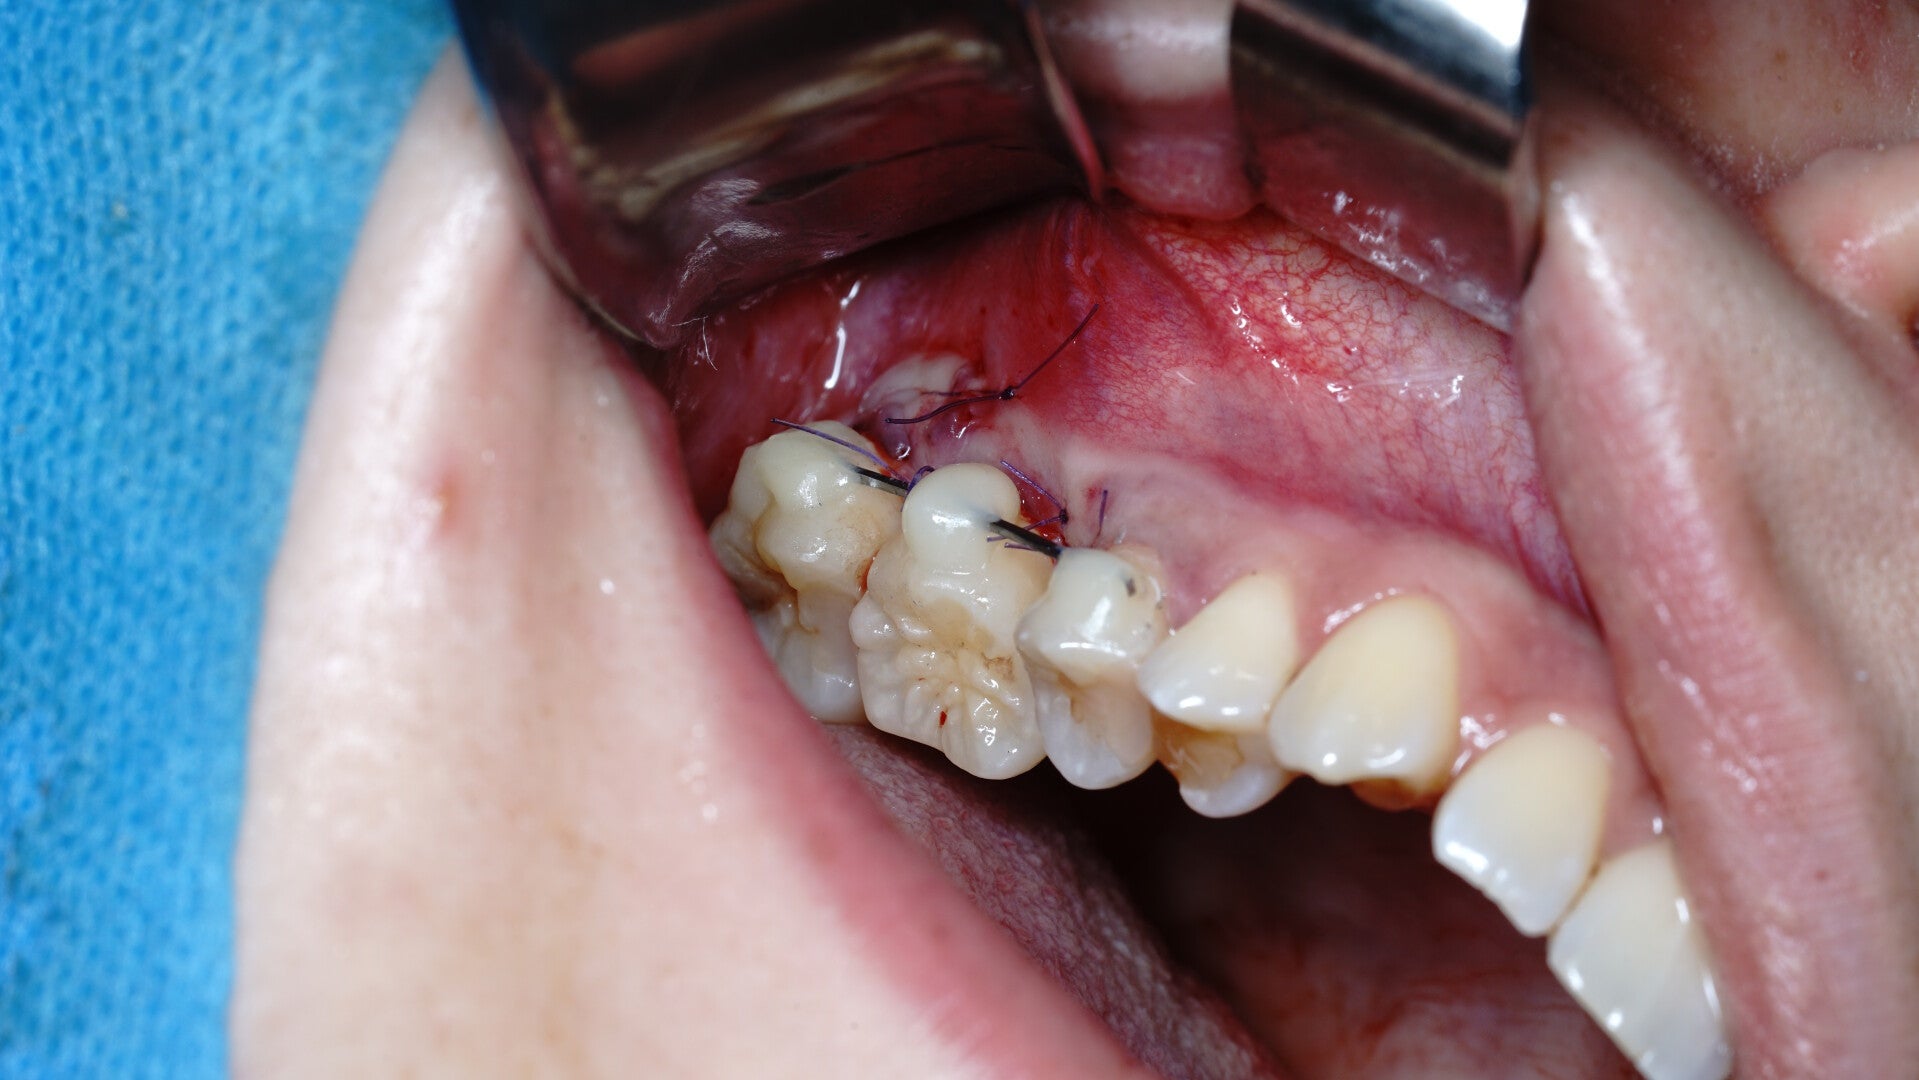

El autotrasplante dental es un procedimiento quirúrgico de alta precisión que consiste en trasladar un diente de una posición a otra dentro de la boca del mismo paciente. Generalmente, utilizamos un diente que no cumple una función vital (como una muela del juicio) para sustituir una pieza perdida o gravemente dañada (como un primer molar).

Esta técnica, realizada por el Dr. Pablo García en Oviedo, combina la cirugía maxilofacial de vanguardia con el respeto máximo por la biología del paciente.

El éxito de un autotrasplante depende del tiempo que el diente permanece fuera de su alveolo. Por ello, en nuestra clínica en Oviedo, utilizamos planificación digital 3D y tomografía computarizada (TAC).

1. Escaneamos tu boca para crear una réplica exacta en 3D del diente que vamos a trasplantar.

2. Preparamos el espacio receptor utilizando la réplica, asegurando un ajuste perfecto.

3. Solo cuando el lecho está listo, extraemos el diente real y lo colocamos en su nueva posición en cuestión de segundos.

Esta tecnología de mínima invasión aumenta drásticamente las tasas de éxito, posicionándonos como un centro de referencia en cirugía oral en España.